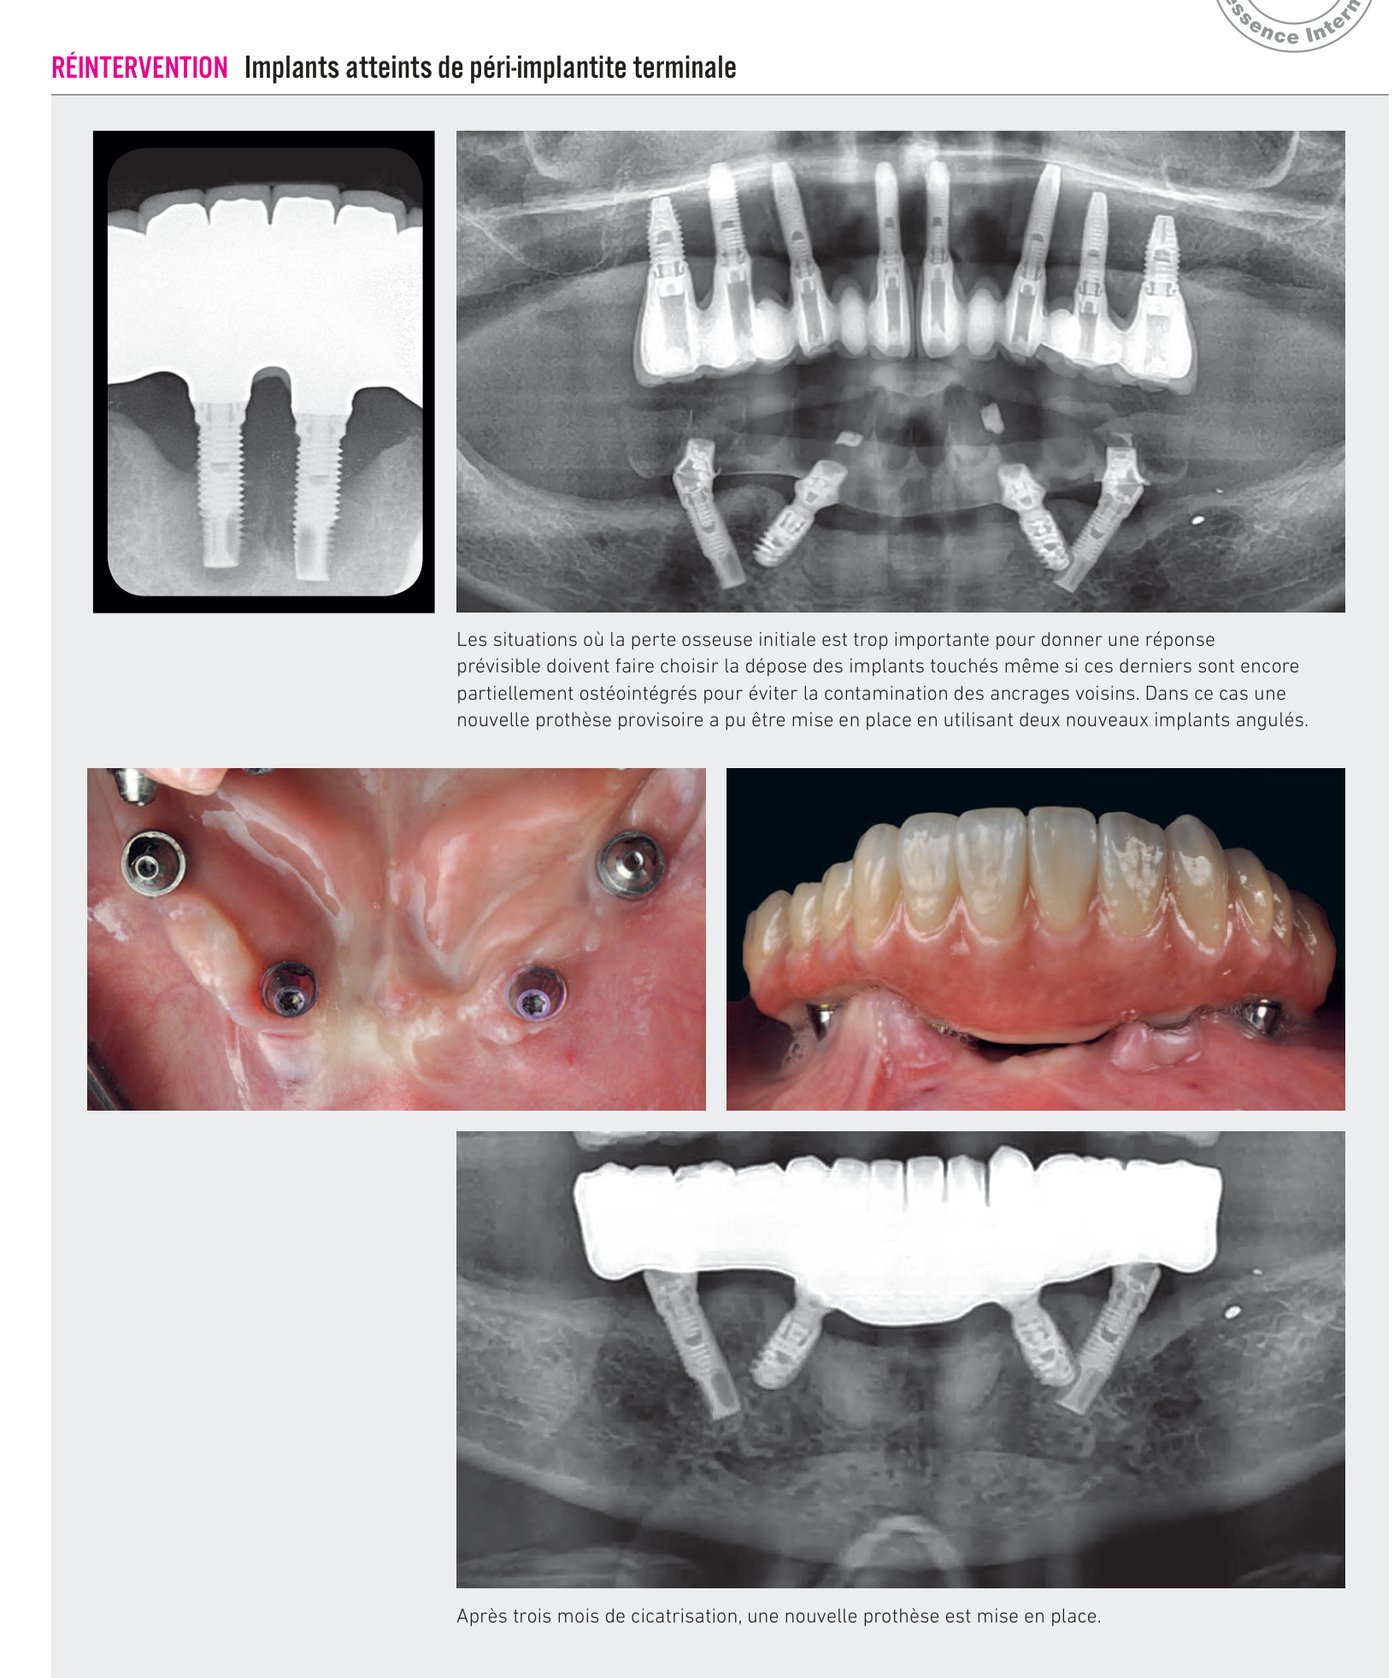

Réintervention — Implants atteints de péri-implantite terminale

Les situations où la perte osseuse initiale est trop importante pour donner une réponse prévisible doivent faire choisir la dépose des implants touchés même si ces derniers sont encore partiellement ostéointégrés pour éviter la contamination des ancrages voisins. Dans ce cas une nouvelle prothèse provisoire a pu être mise en place en utilisant deux nouveaux implants angulés. Après trois mois de cicatrisation, une nouvelle prothèse est mise en place.